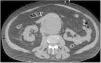

A 71-year-old man with a past medical history of arterial hypertension and a solitary kidney (right kidney) presented with sudden pain in the right iliac fossa radiating to the ipsilateral groin. On examination, a pulsatile mass was palpated in the infraumbilical region, along with a continuous murmur in the mesogastrium. He was admitted to the ICU in a dazed state with significant hemodynamic instability and tachycardia. A basal abdominal CT scan revealed a large infrarenal abdominal aortic aneurysm with signs of perianeurysmal bleeding (arrow in Fig. 1). Following contrast administration, a communication was observed between the right posterolateral wall of the aneurysm and the inferior vena cava, consistent with an aortocaval fistula (arrow in axial view Fig. 2A and coronal view B). These findings were confirmed in the 3D reconstruction performed (Fig. 3). Stent-graft implantation was decided by the heart surgical team. Eventually, the patient developed an episode of ischemic colitis and septic shock, leading to his death 7 days later.